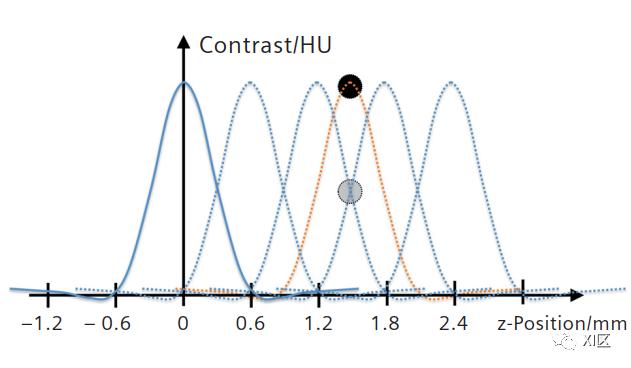

如果完整的探测器宽度范围仅重建64个切片(蓝线),则小结构不会用全对比度描绘。重建128个切片(橙色线)可缩小这些间隙,并确保始终以全对比度描绘精细细节,有效提高z轴方向的空间分辨率。

上图中的蓝线说明了如何在38.4 mm的探测器宽度下重建64个0.6 mm厚的切片。64个切片覆盖整个体积,但在体积中留下间隙,其中0.3 mm球体之类的小对象没有用完全对比度进行描绘。众所周知的事实是,如果现在为探测器覆盖的体积重建128个切片,即每个准直探测器宽度重建两个切片,则这些间隙被填充,而且非常小的物体几乎总是用全对比度来描绘(橙色虚线)。